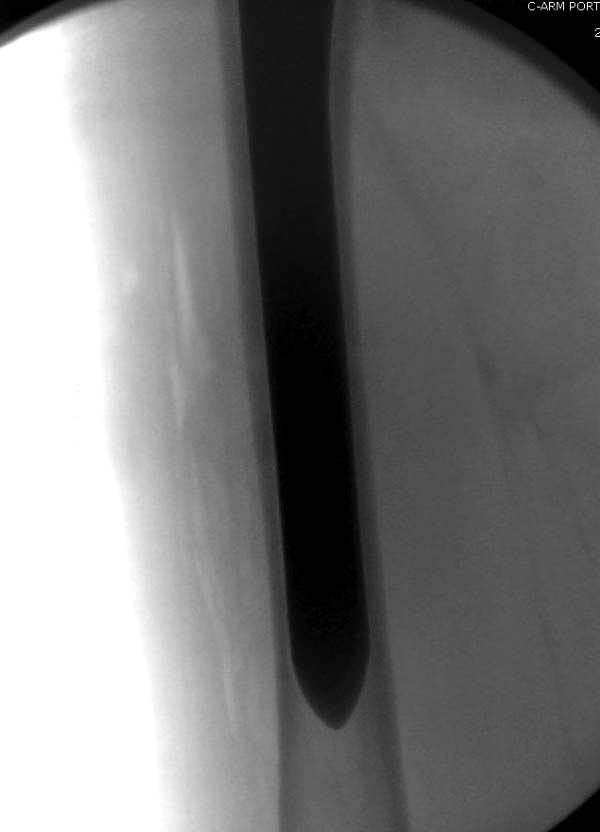

Такие “чужие осложнения” встречаются у всех и представляю банальный случай, который шаг за шагом показано как перерос в более сложный процесс... Больная 70 лет, множественные ко-морбидности, чрезвертельный перелом первоначально фиксирован Гамма 3. Осложнение в течение 6 недель, ревизия тотальной артропластикой и во время установки ножки обнаружена трещина диафиза (17), из малого доступа фиксация алло-графтом.